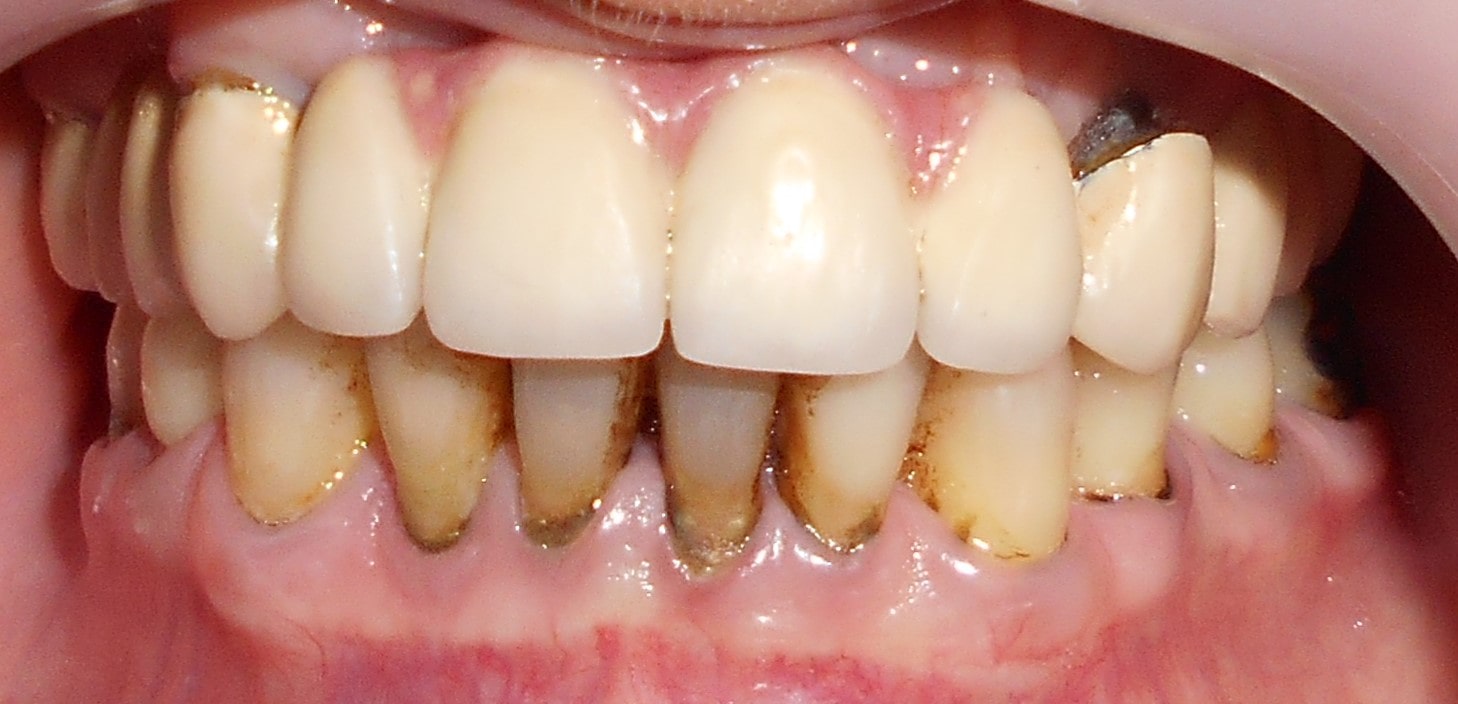

Pacijent 3

Pacijent dolazi sa starim mostovima i izraženom parodontopatijom u donjoj vilici. Urađeno je skidanje postojećih mostova i istovremena ekstrakcija svih parodontopatičhin zuba uz ugradnju sedam implantata u gornjoj vilici i pet implantata u donjoj vilici. Pacijent je nakon tri dana bio privremneo protetski zbrinut sa fiksnim privremeni krunicama koje su fiksirane na tek ugrađenim implantaima. Nakon četiri meseca je izrađen fiksni cirkonijum kermički- bezmetalni most u gornjoj i donjoj vilici. Rad uspešno završen pre tri godine.